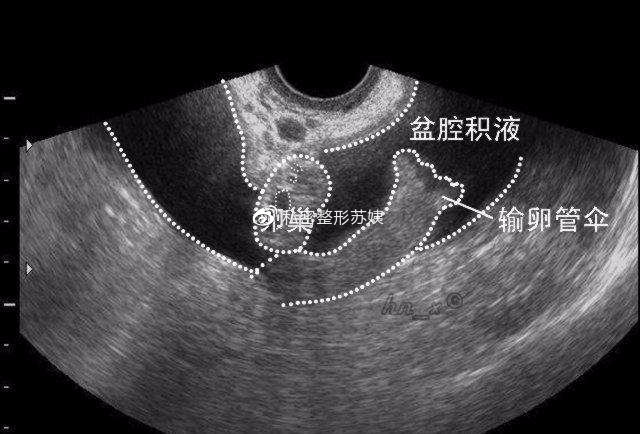

盆腔积液(pelvic effusion)是一种表现而不是一种疾病,确切地说是影像学对盆腔内液体的一种描述。可分为生理性盆腔积液和病理性盆腔积液两种。病理性盆腔积液可发生在盆腔炎、附件炎或子宫内膜异位症之后,为盆腔炎的主要影像学特征。

盆腔积液的位置多发生在子宫直肠陷凹等盆腔内位置较低处,妇科常用的有效检查手段是B超,可以较准确的判断积液的量。可结合详细病史、症状以及体症等,明确是正常积液还是异常积液。如确诊为异常积液则要明确导致积液的原因,病因性诊断是关键。抽取积液是明确诊断的主要手段。